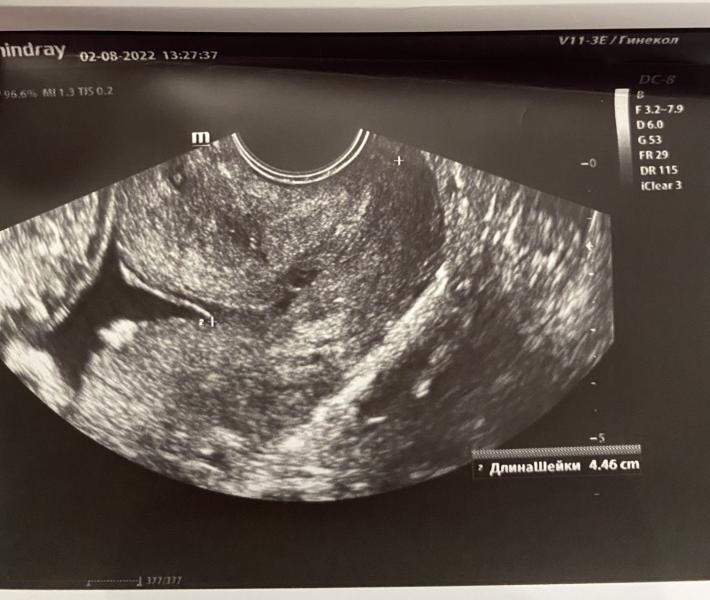

История такая: писала уже здесь, что со 2 скрининга намеряют мне короткую шейку (29мм) на приеме в жк отправили на узи 3 недели назад была 27. Дали снимок (на нем я вообще шейку не вижу) фото 1.

Обеспокоенная этим вопросом, написала сюда. Многие посоветовали гуру по коротким шейкам - Судаков- врач кмн, принимает в женской клинике.

Была на приеме, немного осталась в противоречивых чувствах. Вроде все расспросил, очень больно посмотрел на кресле, пытался почувствовать откры...